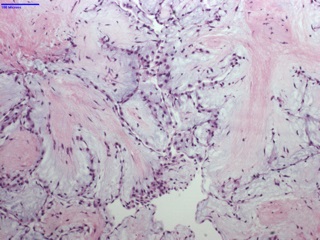

Histologically, they are composed primarily by collagen and elastin at the base with abundant mucopolysaccharide stroma, and outer endothelium expressing vimentin, factor VIII and CD34. The vasculature is minimal while myxomas (the main differential) are highly vascular lesions with typical “myxoma” cells and very rarely occur in heart valves.